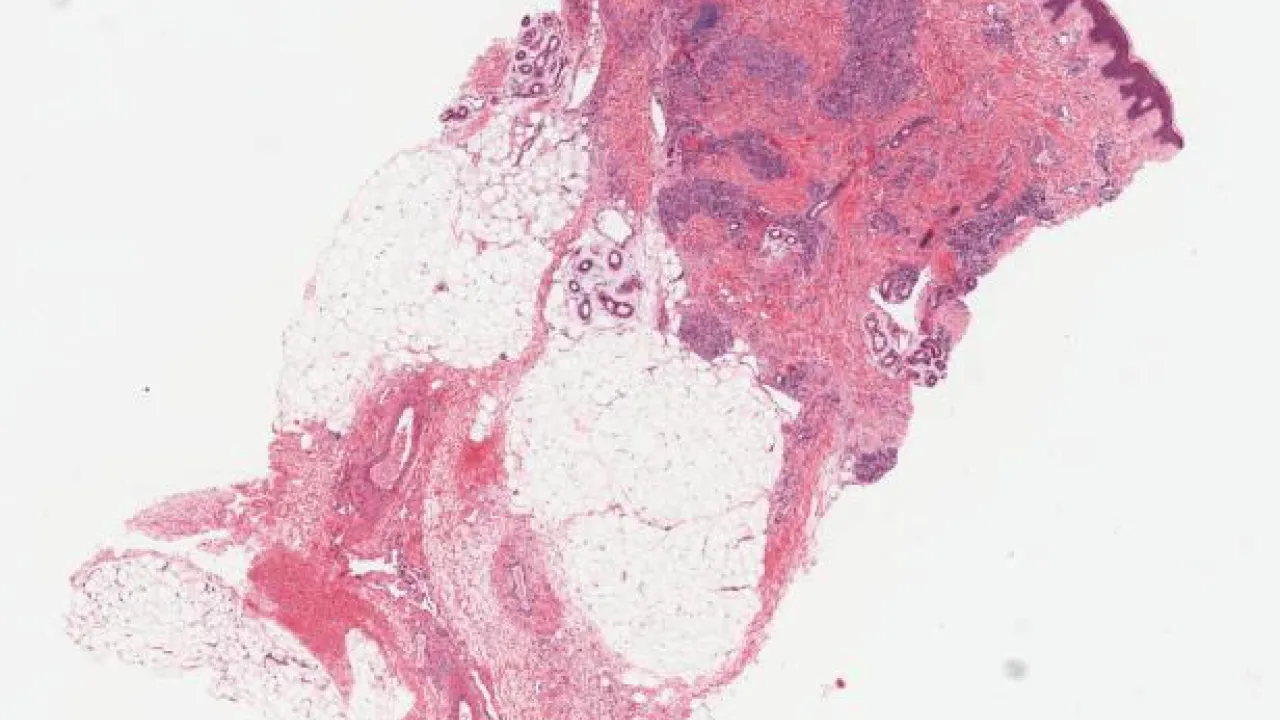

Soft tissue, lipoblastoma